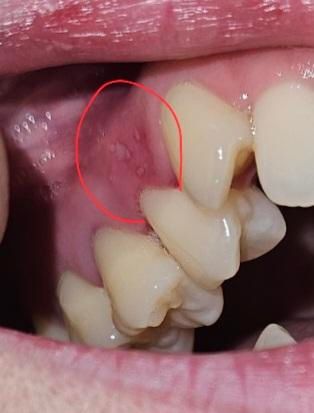

레진한 어금니 윗 잇몸 상처? 파임? 염증? 질문입니다.

5일전 레진한 어금니 윗 잇몸에 상처? 파임? 염증? 뭔진 모르겠는데 양치하고나니 해당 잇몸이 약간 따가움이 있어요. 혀로 문질러보면 울퉁불퉁해요..

• 2번 째 사진

잇몸 사진으로 봐서는 구내염의 양상이고, 며칠 전 치과치료를 받으셨다고하니 해당 부위 잇몸이 자극되거나 피로하여 그럴 수 있습니다. 일주일내로 자연스럽게 완화될 것 같습니다.

레진치료를 할때 잇몸에 자극이 있었다면 구내염등이 생길수 있습니다. 이런 증상은 대부분 2주이내에 없어지게 됩니다.

불편감이 크다면 오라메디와 같은 구강점막연고를 사용해 보세요.

레진 치료 시, 치료 도구나 재료가 잇몸에 일시적으로 자극을 줄 수 있습니다. 치료 후 주변 잇몸이 일시적으로 붓거나 예민해질 수 있으며, 이는 시간이 지나면서 가라앉기에 크게 걱정하지는 않으셔도 됩니다.

해당부위가 자극되지 않게 부드러운 칫솔로 양치를 하여 관리를 하길 권합니다.

만약 따가움이 심해지거나, 붓기가 지속된다면 치과 진료를 받길 권합니다.